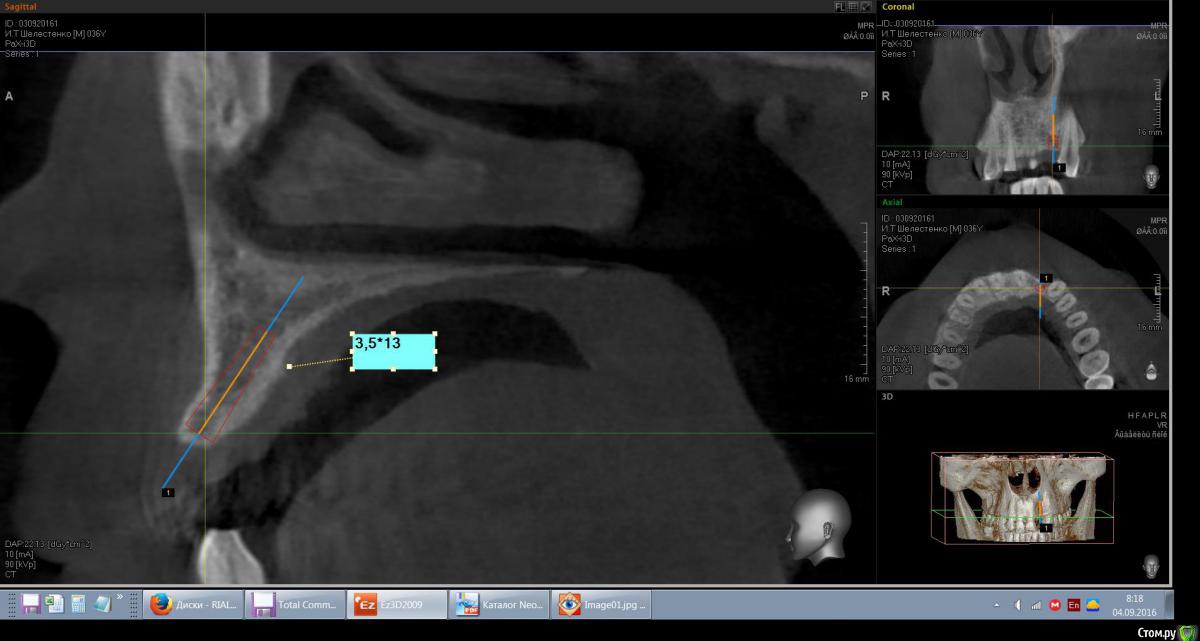

mann Опубликовано 4 сентября, 2016 Автор Поделиться Опубликовано 4 сентября, 2016 Доброе утро!Имеем такую ситуацию. Как лучше и правильно расположить имплант в данной ситуции? Ссылка на комментарий

red_butler Опубликовано 4 сентября, 2016 Поделиться Опубликовано 4 сентября, 2016 вот видите костное предложение на самом деле лучше. Только не нужно так небно ставить. Если сомневаетесь сделайте шаблон или пригласите на операцию ортопеда. И трансп добавьте. Ссылка на комментарий

red_butler Опубликовано 4 сентября, 2016 Поделиться Опубликовано 4 сентября, 2016 а что это? трансплантат.Мне больше нравится позиция на втором снимке, только вестибулярнее и не так глубоко, и я бы ложе готовил эспандерами или чуток расщепился бы Ссылка на комментарий

kamranchick Опубликовано 4 сентября, 2016 Поделиться Опубликовано 4 сентября, 2016 а что это?Т.е.правильным будет как на первом фото и угловой абатмент?мясца с бугорка, если постарайтесь то можно даже прямой абатмент сделать. при позиционировании смотрите на нижние антагонисты Ссылка на комментарий

Эдгар Витальевич Опубликовано 22 октября, 2016 Поделиться Опубликовано 22 октября, 2016 Имплант 3.5мм не узковат будет? Такая же операция предстоит, ширина кости также 4.5 мм. Я планировал 4 мм ставить и костную пластику-титановую мембранку на имплант закрепить под фрмирователь. Ссылка на комментарий